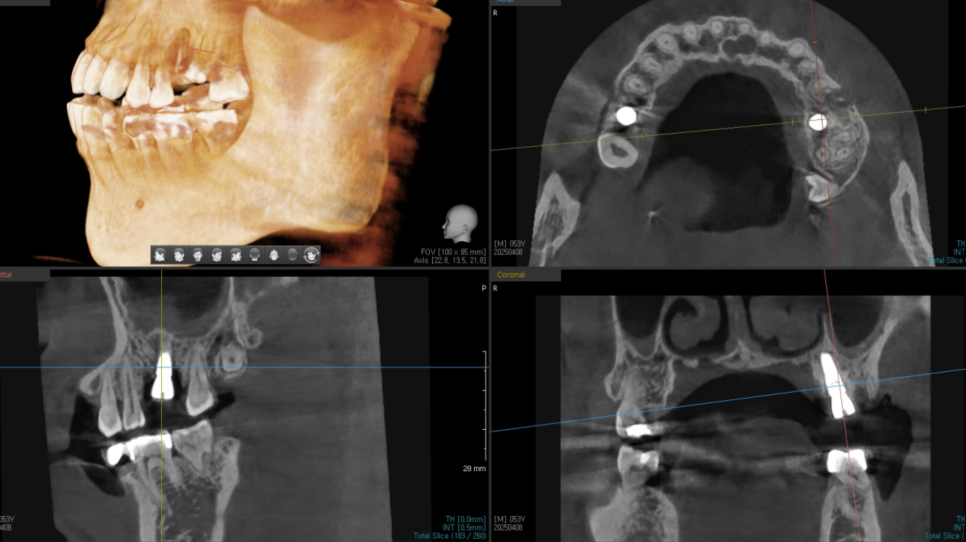

임플란트 식립 시기는 x-ray, ct등을 통해 결정됩니다.

보이지 않는 잇몸 내부안에 잇몸 뼈의 양과 질

염증 유무, 상태 등을 자세하게 관찰 할 수 있는 것이 x-ray입니다.

250409 잇몸 내부 뼈를 확인할 수 있는 ct

검사 결과에 따라 발치 당일 바로 진행하거나,

회복 시간을 둔 후 식립 시점을 계획하는 방식으로 나뉘게 됩니다.